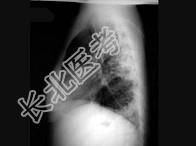

- 单项选择题女,18岁, 1年前患肺结核经抗结核治疗后好转,现发热、咳嗽、体重下降, 结合CT图像,最可能的诊断是 ( )

A、肺结核

B、肺炎

C、肺脓肿

D、肺转移瘤

E、细支气管肺泡癌